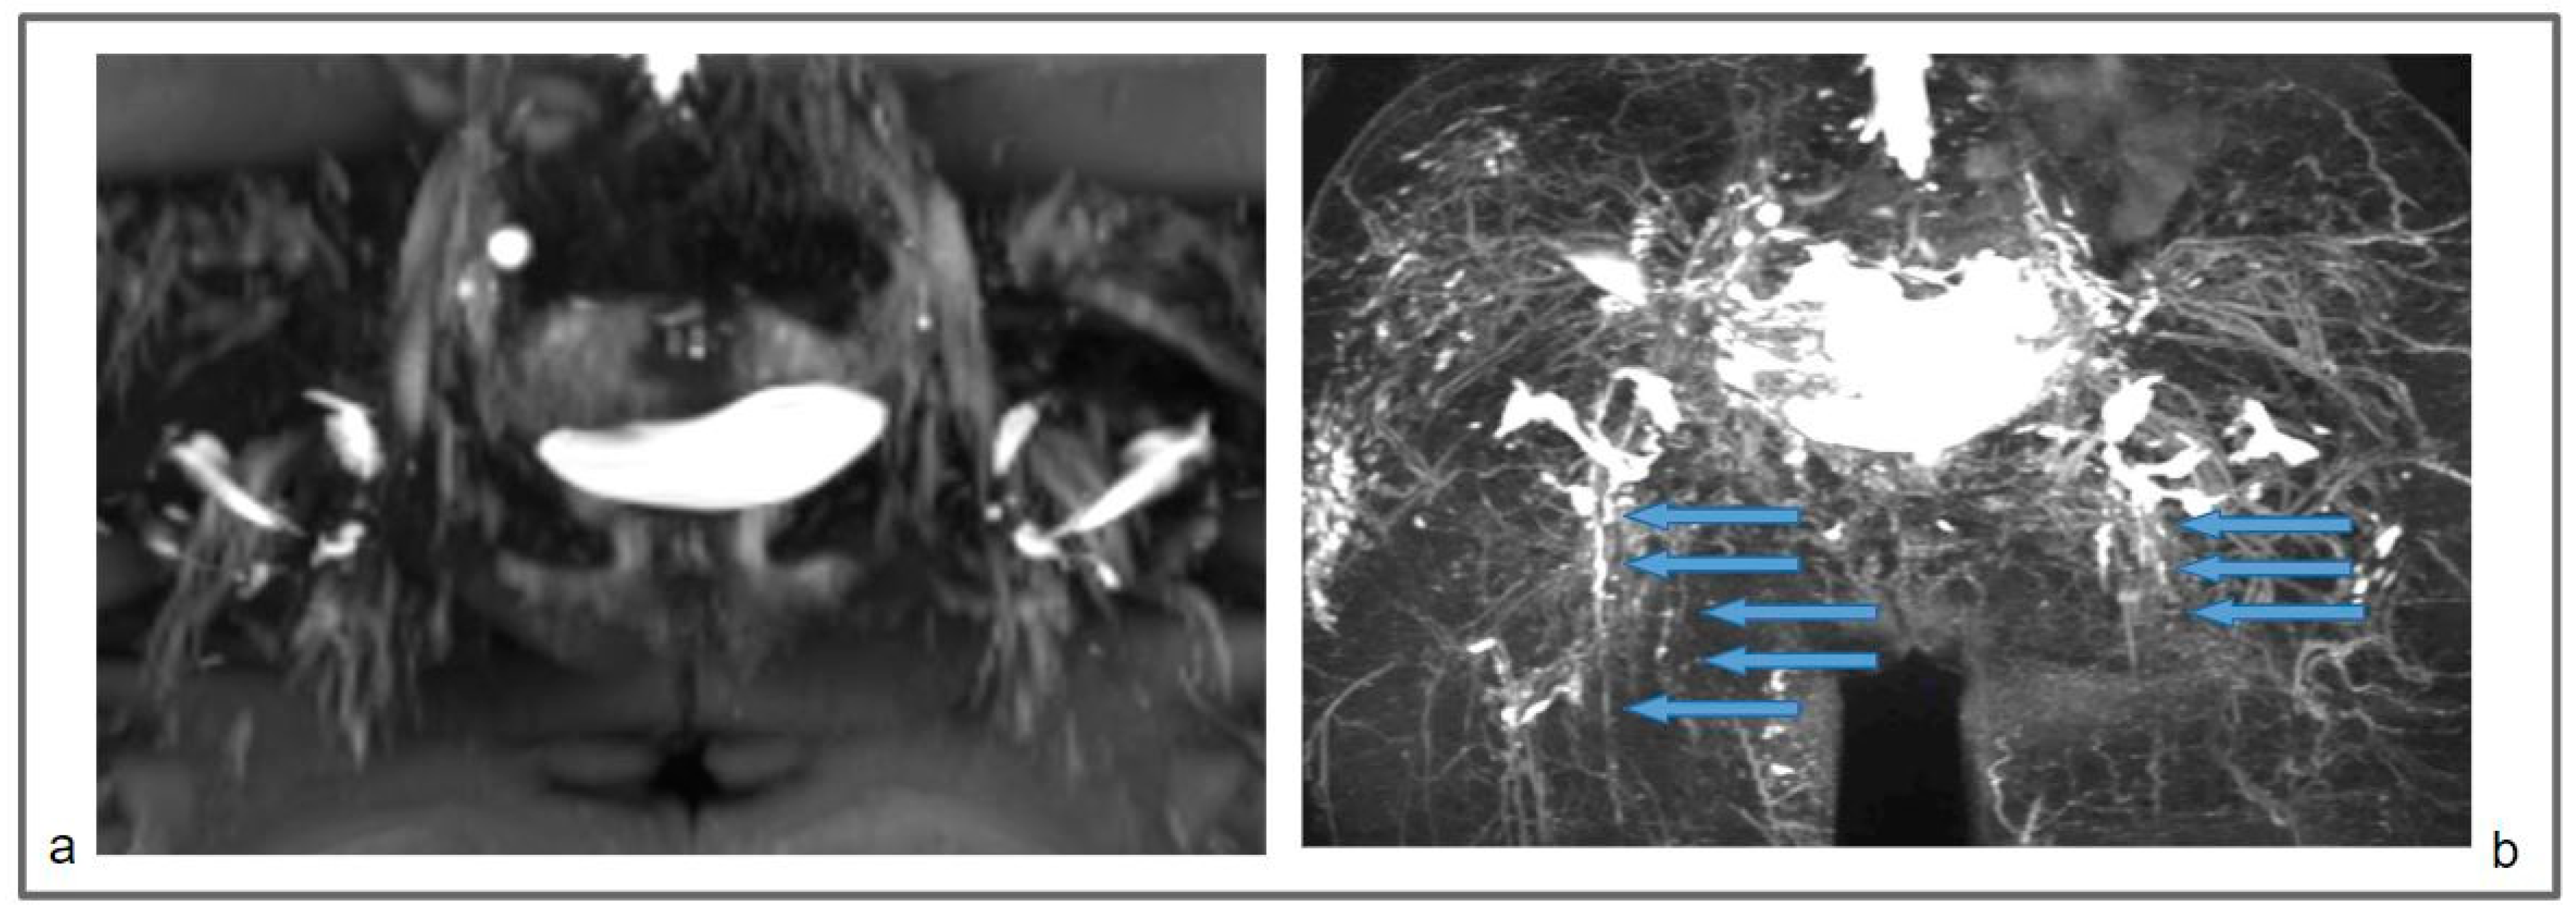

Figure 4.

Patient 1: Preoperative non-contrast MR lymphography (a) and at 1-year follow-up (b). MRI was based on 3D high-spatial-resolution, heavily T2-weighted acquisitions, resulting in a signal loss in the tissue background (like the sequences applied in cholangiopancreatography and MR urography), and enhancement of static fluids like epifascial fluid collections and lymphatic vessels. The follow-up demonstrates the appearance of new inguinal lymphatic vessels (b; blue arrows), that were not visible in the preoperative MR lymphography.